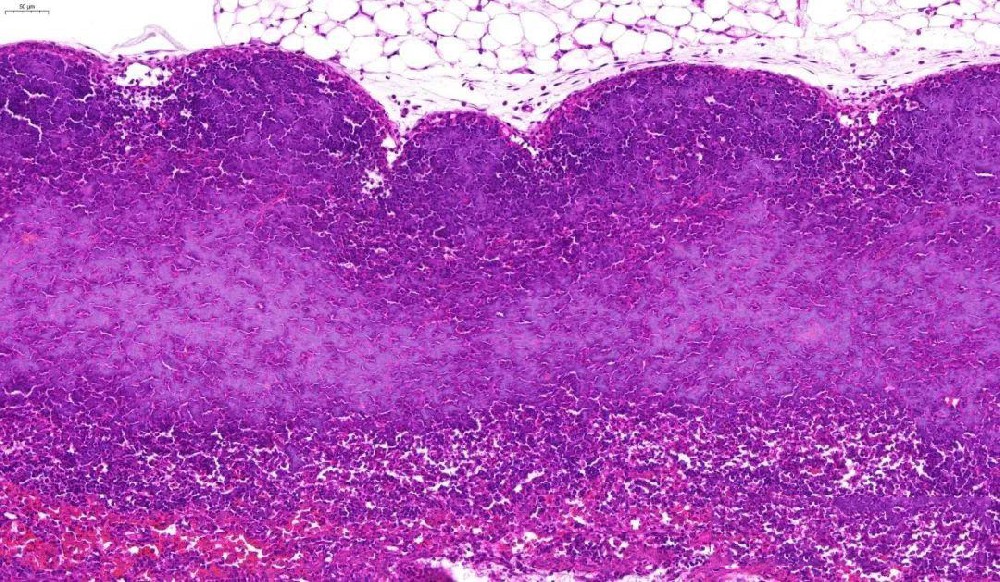

(一)实验目的通过苏木素(碱性染料)和伊红(酸性染料)对组织切片进行染色,使细胞核、细胞质呈现不同颜色,清晰显示组织细胞的形态结构、排列方式,为病理诊断提供基础依据。(二)实验材料1. 样本:已烤好的病理···